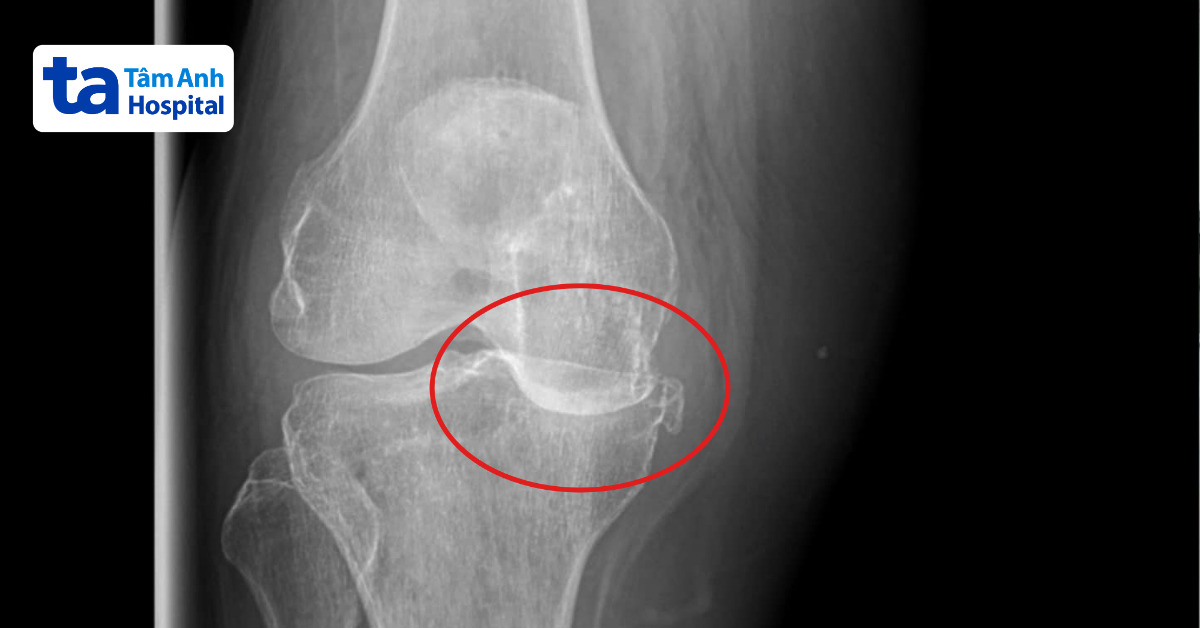

Kết quả chụp X-quang tại Bệnh viện Đa khoa Tâm Anh TP HCM cho thấy chân phải của bà Thanh bị lỏng lẻo dây chằng, thoái hóa khớp gối giai đoạn cuối, sụn khớp tiêu biến hoàn toàn khiến hai đầu xương khớp gối va chạm vào nhau khi di chuyển. Tình trạng này kéo dài gây biến dạng khớp, chân phải vẹo trong nặng, gối ưỡn khoảng 45 độ.